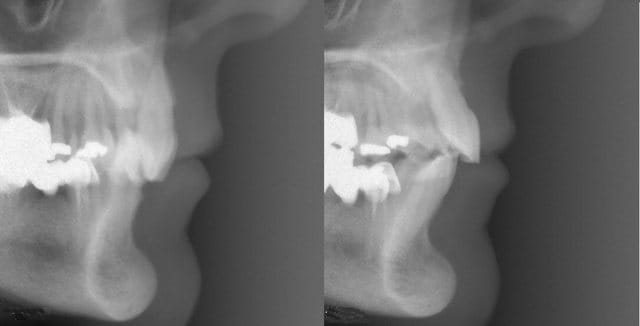

En voici un exemple, c'est un traitement que j'ai réalisé il y a quelques années chez un adulte de 53 ans..

Ce qui est intéressant dans ce cas, c'est que l'ingression s'est accompagnée d'un recul radiculaire des incisives non explicable par la mécanique utilisée (très simple par ailleurs).

Le fil que j'avais utilisé était rond, ce n'est pas lui qui a pu reculer les racines.

Ce n'est pas non plus l'effet de la direction de la force d'ingression, comme je le montre sur le schéma. On aurait dû avoir une vestibuloversion coronaire pas un recul des apex. Le centre de résistance de la dent était très haut parce qu'il y avait un support osseux très réduit.

Il faut donc chercher ailleurs l'explication, et c'est là qu'on pourrait faire un parallèle avec le cas de Jeff…